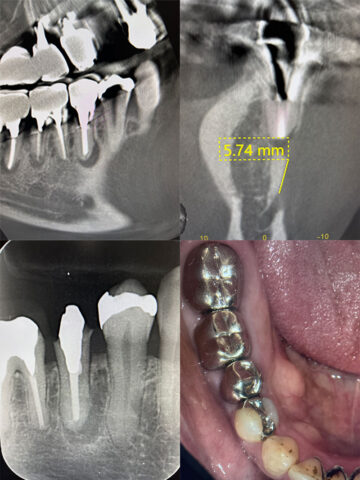

こちら並列の術前です。

オトガイ神経に近接しており、歯根端切除をすると神経損傷のリスクがある症例です。 -